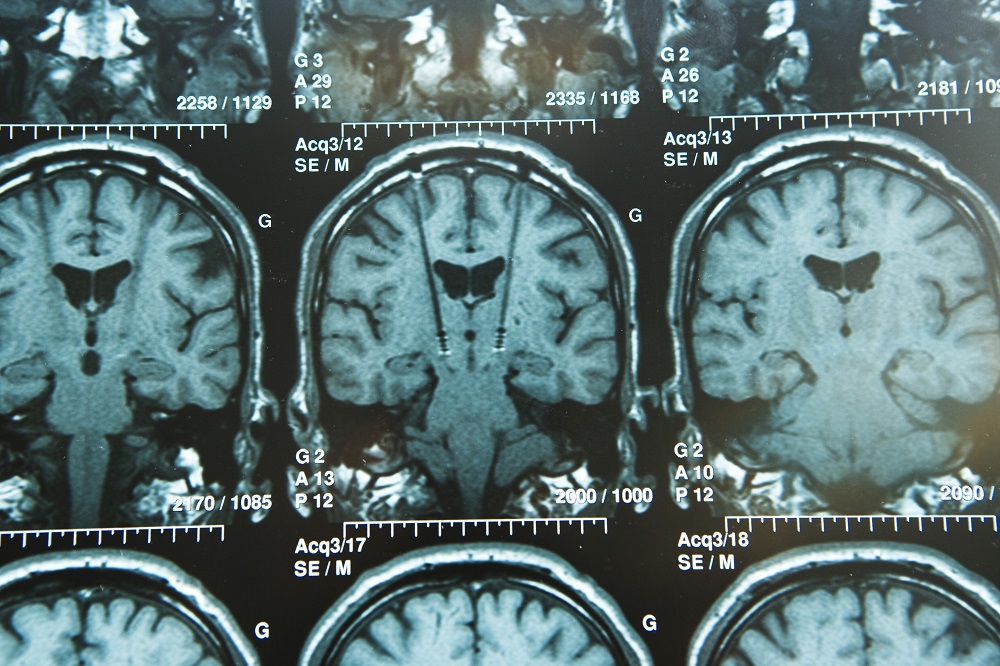

Matthew A. Brodsky, MD, an associate professor of neurology and medical director of the DBS program at Oregon Health & Science University in Portland, recently led a study on one of the new approaches. In research published in Neurology in November 2017, his team compared the use of intraoperative imaging guidance to confirm electrode placement in asleep patients undergoing DBS with the use of microelectrode recording to confirm placement in awake patients, the current standard practice.

When they compared 6-month outcomes in the 69 patients, they found greater improvements in cognition, communication, speech, and dyskinesia during on time in the asleep patients, although both groups showed improvement in quality of life (QoL).

We had a lot of skeptics who asked, ‘”Well, how do you know you’re in the right spot if you don’t do the microelectrode recording or if you don’t wake up the patient in the OR [operating room] and do the test stimulation?” But it turns out that the patients in our study did at least as well as patients who were asleep with regard to improvement in tremor, slowed movement, and muscle rigidity, and in some respects patients actually had better outcomes, for example, in speech fluency. Getting people to adapt to a different method can take time, but I think we will eventually see procedures change, and that is going to provide a QoL for patients.